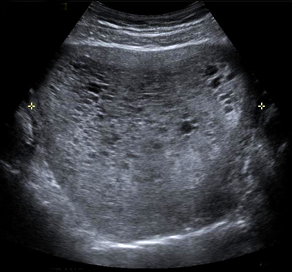

Common Ultrasound Procedures

UCSF’s ultrasound subspecialty provides the Bay Area’s most advanced and multidisciplinary ultrasound services. We offer, for example, the integrated services available for fetal therapy and UCSF’s outstanding ultrasound disease diagnosis, and the highest levels of real-time ultrasound imaging accuracy for transplant surgery.